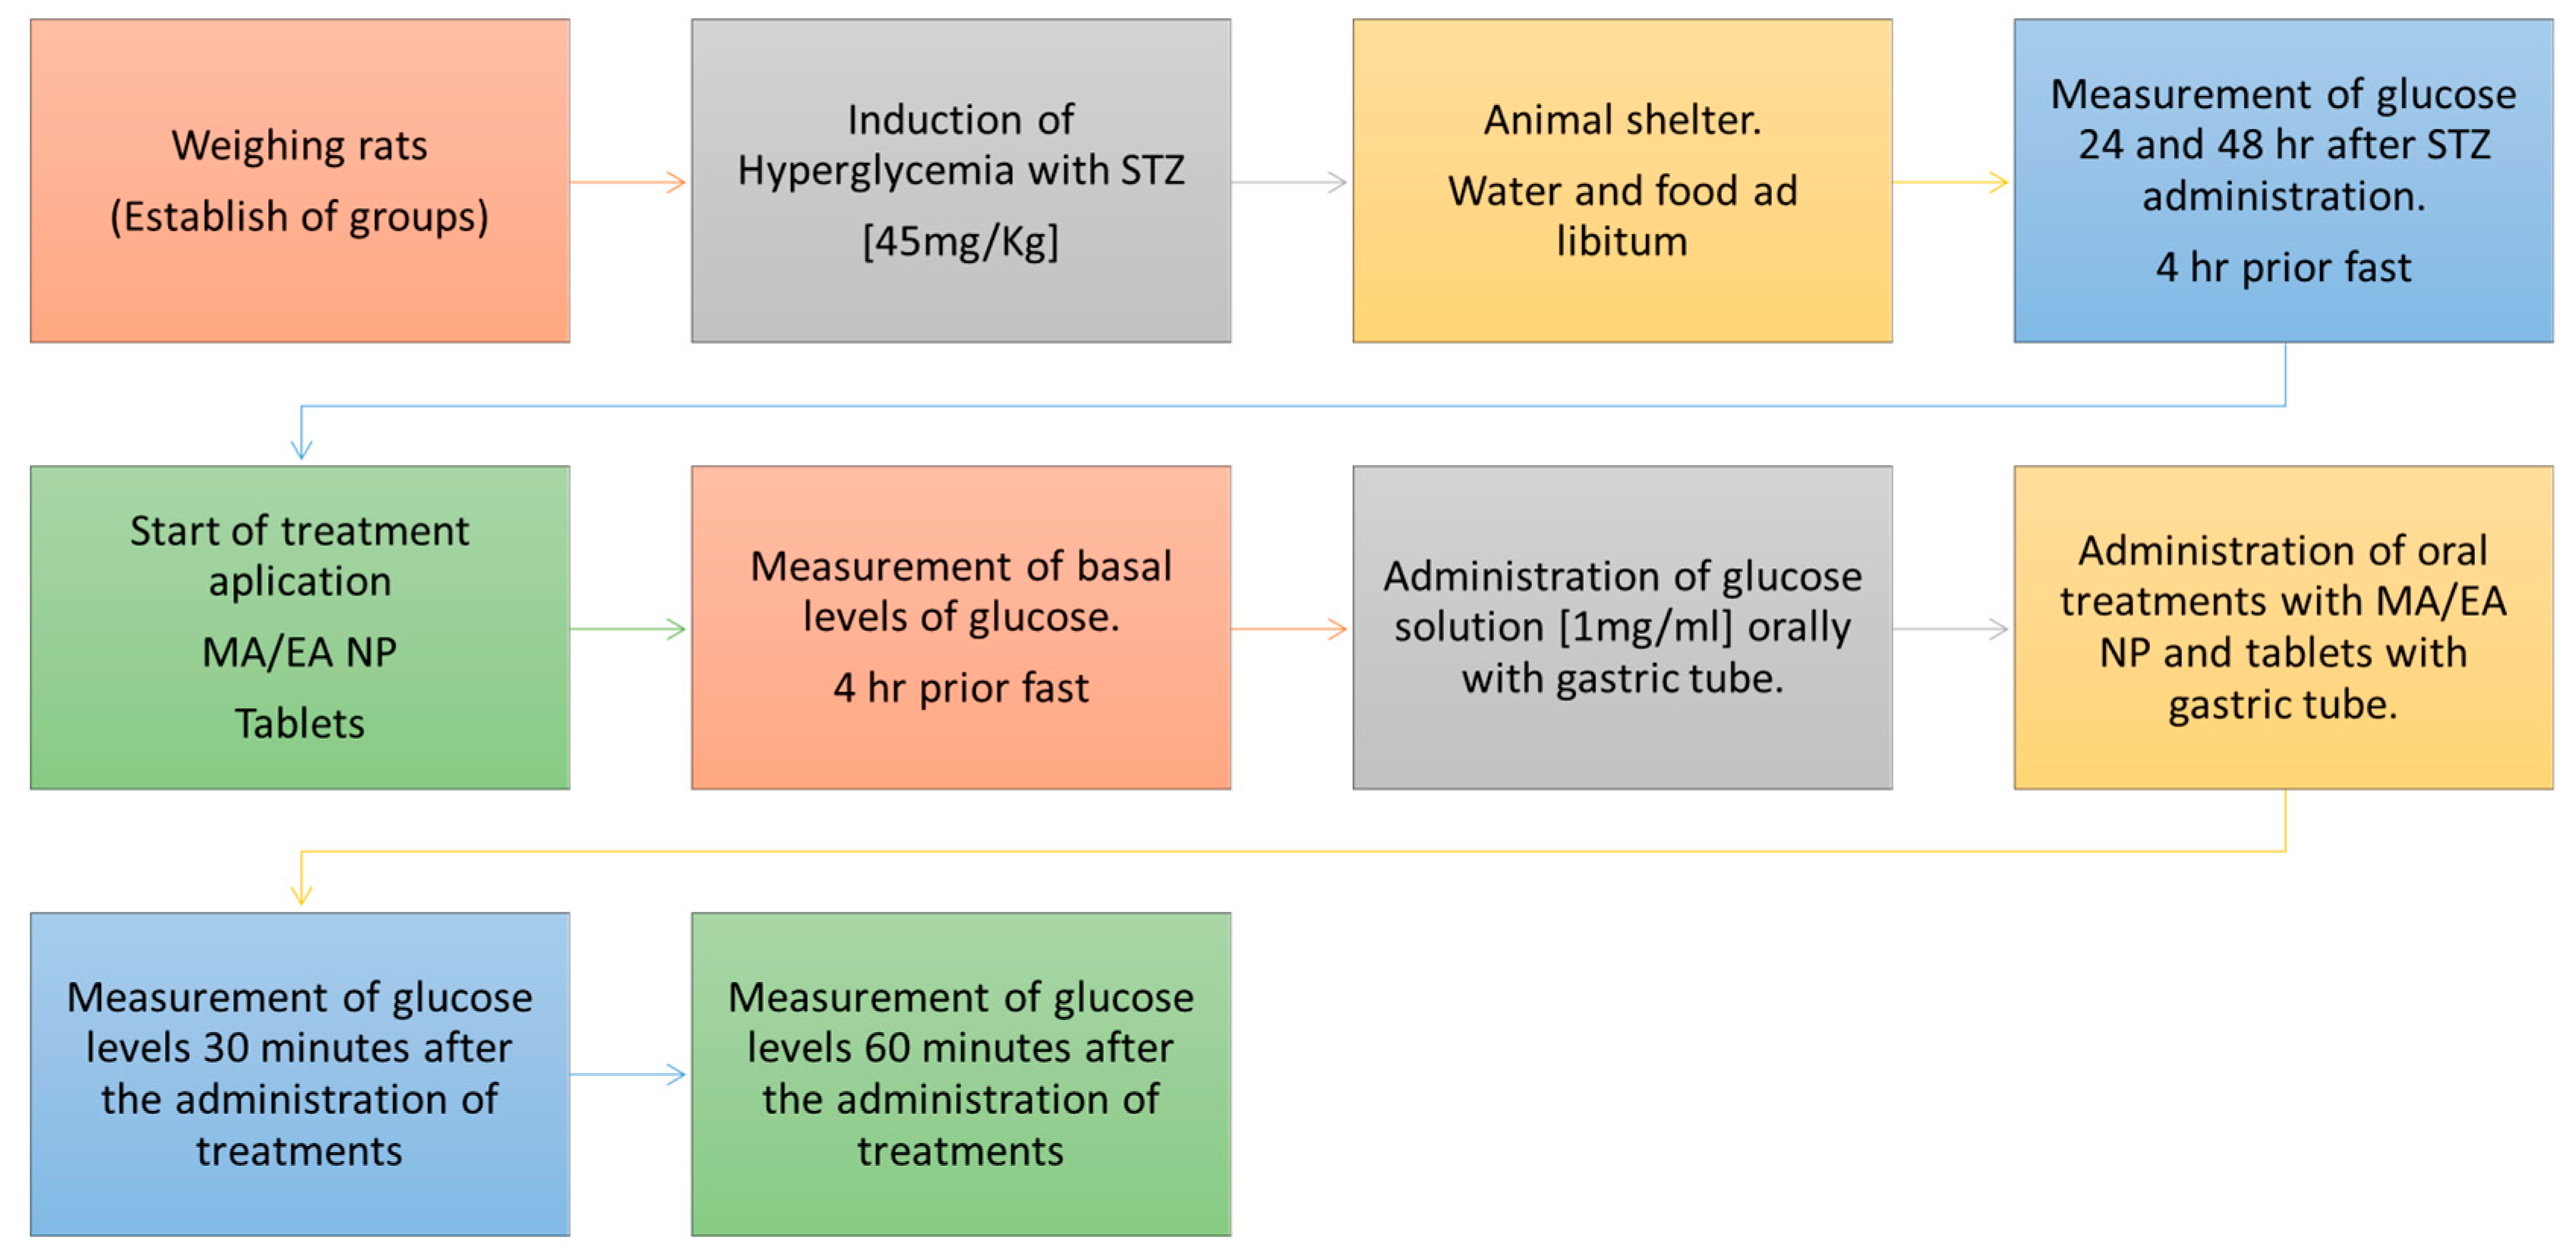

2.7. In Vivo Model

3.1.7. In Vivo Tests

| Animals Were Divided into 5 Different Groups with 5 Individuals Each as Follows: |

|---|

| Group 1: untreated diabetic rats |

| Group 2: diabetic rats with conventional pharmaceutical form (tablets) |

| Group 3: diabetic rats administered with NP without glibenclamide |

| Group 4: diabetic rats administered with NP with glibenclamide |

| Group 5: control |